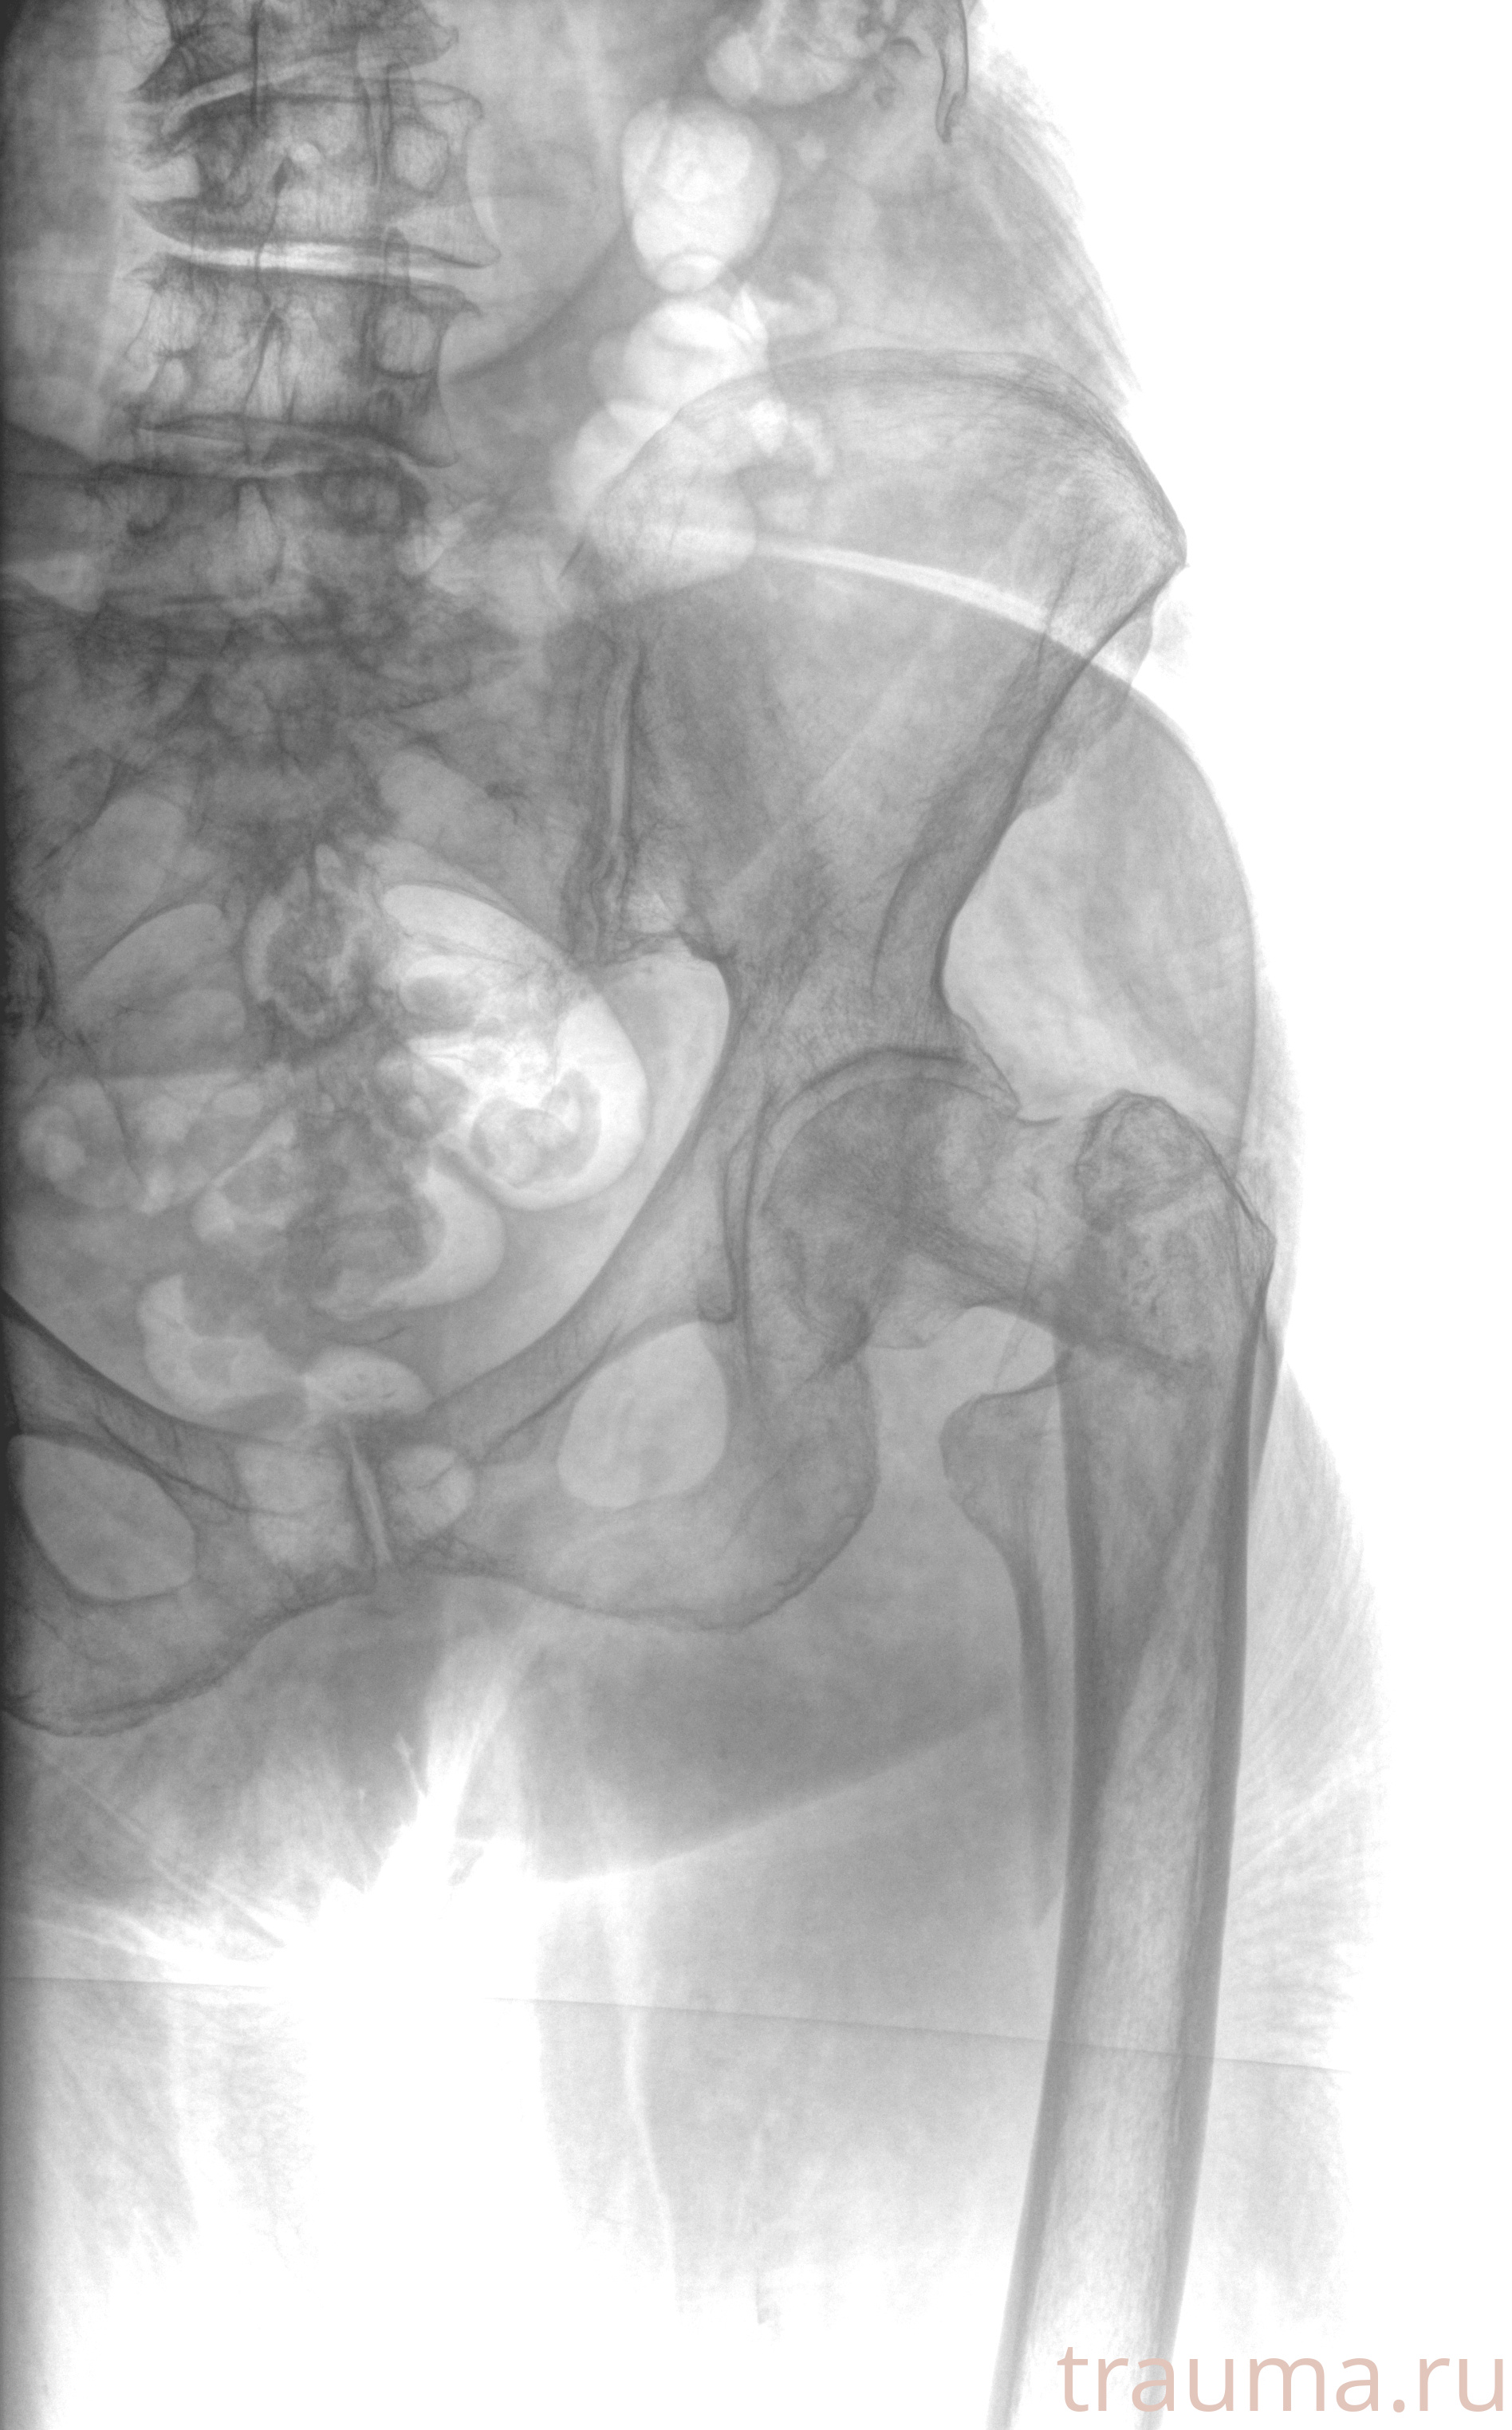

Рентгенограммы

Рентген на дому: по вашему адресу приезжает врач-рентгенолог, травматолог-ортопед с мобильным рентгеновским аппаратом, проводит диагностику травмы или заболевания, делает необходимые рентгенограммы, дает рекомендации по дальнейшему лечению. Получить качественные снимки в домашних условиях возможно благодаря уникальной методике, разработанной МосРентген Центром для института  Склифосовского